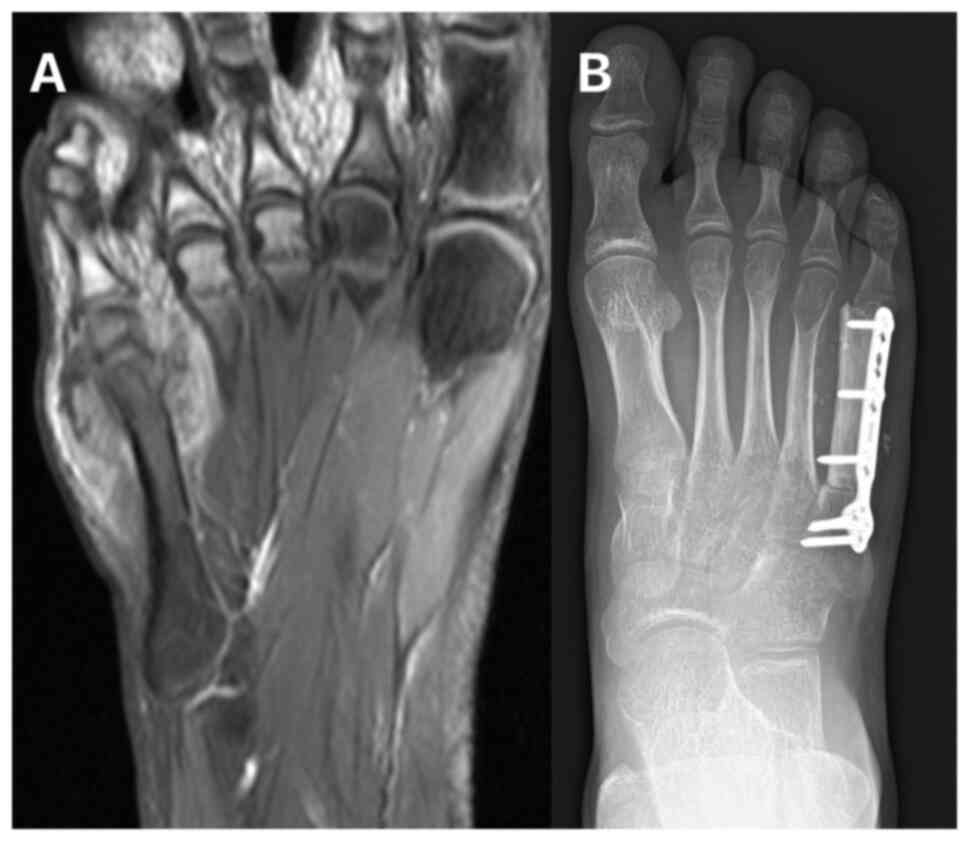

In January 2019, an 11-year-old female was referred to the Masaryk Memorial Cancer Institute Sarcoma Center with a 2-month history of pain in the right foot. MRI scans showed a 3 cm thickening of the bone in the V. metatarsal diaphysis (Fig. 11). The histopathology report showed an intermediate-grade periosteal osteosarcoma (Fig. 12). The patient had no lymph node involvement or metastases. The Musculoskeletal Tumor Committee recommended en bloc resection with bone allograft reconstruction using a plate. The final histopathology report confirmed the initial findings from the biopsy (Fig. 13). After 2 years, a follow-up plain radiographs showed ossification on the allograft surface (Fig. 14), leading to a biopsy to check for any signs of local recurrence. The biopsy results showed no evidence of malignancy (Fig. 15). At the time of writing, the patient completed 5 years of follow-up appointments with no signs of disease recurrence.

Case 3. (A) MRI showing a periosteal osteosarcoma of the fifth metatarsal. (B) Postoperative radiographic imaging following complete resection and reconstruction with a bone allograft and plate fixation.